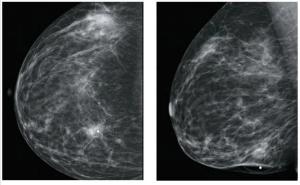

A 46-year-old woman had a routine screening mammogram that showed new calcifications in the posterior left breast. A diagnostic mammogram showed several small punctate calcifications, and a 6-month interval follow-up was recommended.

A 40-year-old woman noted a large mass in her right breast. A diagnostic mammogram and ultrasound confirmed a 3.4-cm mass with associated microcalcifications.